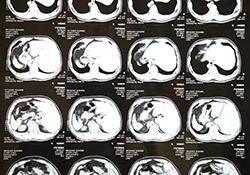

内臓脂肪が蓄積し、脂肪細胞が肥大すると、この物質の分泌異常が起こり、「中性脂肪値」、「血糖値」、「LDLコレステロール値」、「血圧」が高くなることも確かめられています。メタボ度が高い人ほど、そうした異常のリスクが高まるといわれています。

これらの数字が気になる人は、何よりもまず、内臓脂肪(内臓の周囲に付いた脂肪)を減らすことを考えることが得策なのです。

皮下脂肪(つまむことができる、お腹の皮膚の下にある脂肪)を減らすには努力と忍耐が必要ですが、内臓脂肪はたまりやすい反面、落ちやすい特徴があります。